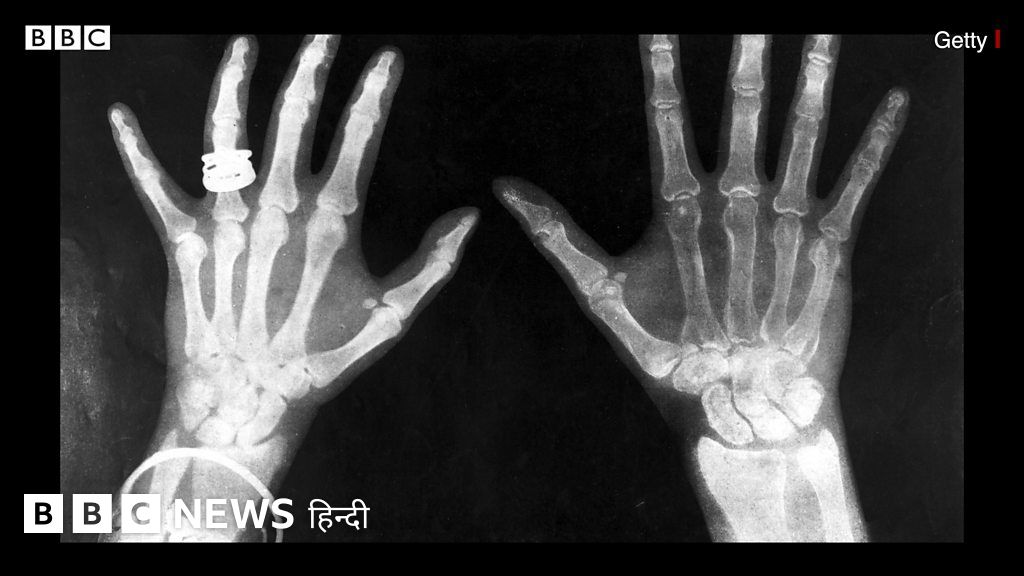

काले रंग की फ़िल्म पर दिखती शरीर की हड्डियों से यह पता लगाया जाता है कि कहां पर चोट आई है वो चोट कितनी गंभीर है.

क्रूक्स ट्यूब असल में गैस पर रिसर्च करने के लिए इस्तेमाल की जाती थीं. यह एक तरह की वैक्यूम सील्ड कांच की ट्यूब होती है. जिससे बिजली पास की जा सकती है तो उसका रंग बदल जाता है. तो ऐसे में वैज्ञानिक विलहेम ने महसूस किया कि उनकी क्रूक्स ट्यूब से कई तरह तरंगे पूरी लैब में फैल रही हैं. यहां तक कि जब उन्होंने क्रूक्स ट्यूब को एक कार्डबोर्ड से छिपाने की कोशिश की तब भी वो रेज़ उससे कार्डबोर्ड के आर-पार हो गईं. विलहेम यह देखकर काफी हैरान रह गए और उन्होंने इन रेज़ को नाम दिया एक्स-रे. इसकी वजह यह थी कि उन्हें इन रेज़ का नाम नहीं पता था इसलिए उन्होंने इन्हें 'एक्स' नाम दे दिया.विलहेम ने अपने एक्सपेरिमेंट को एक कदम आगे बढ़ाते हुए इन रेज़ को अपनी पत्नी के हाथ से गुज़ारा, और उसके बाद जो हुआ उसे देखकर वो हैरत में पड़ गए. वो अपनी पत्नी के हाथ की त्वचा के भीतर देख पा रहे थे. वो अपनी पत्नी के हाथ की हड्डियों और शादी की अंगूठी देखने में कामयाब रहे. ऐसा पहली बार था जब किसी इंसानी जिस्म के भीतर इस तरह देख पाना संभव हो सका. विलहेम को अपनी इस अनूठी खोज के लिए साल 1901 में फिजिक्स का नोबेल पुरस्कार मिला.